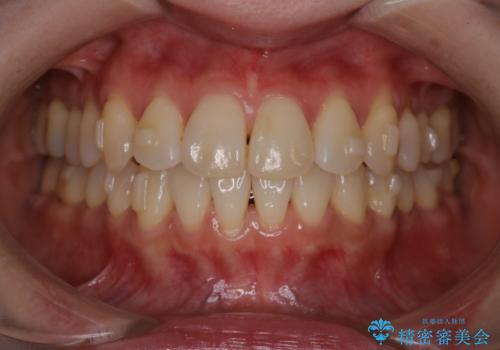

【インビザライン】かみ合わせを整えたい

- インビザラインで非抜歯治療を行いました。IPRと拡大をし、叢生、咬合をきれいにしました。

主訴であったかみ合わせを正しい位置に動かし、バランスよくかめるようになりました。矯正治療終了後にメタルインレーをセラミックインレーに替えました。